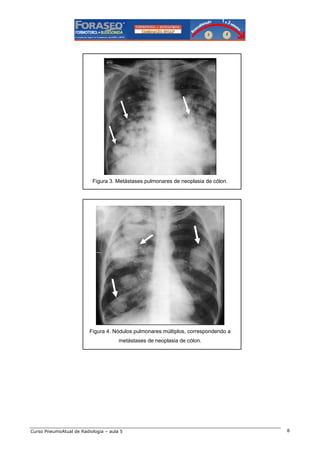

Figura 3. Metástases pulmonares de neoplasia de cólon.

Figura 4. Nódulos pulmonares múltiplos, correspondendo a

metástases de neoplasia de cólon.

Com relação às metástases (figuras 2 a 5), devemos sempre pensar nas principais causas de

comprometimento secundário pulmonar: mama, rim, tiróide, laringe, cólon e útero.